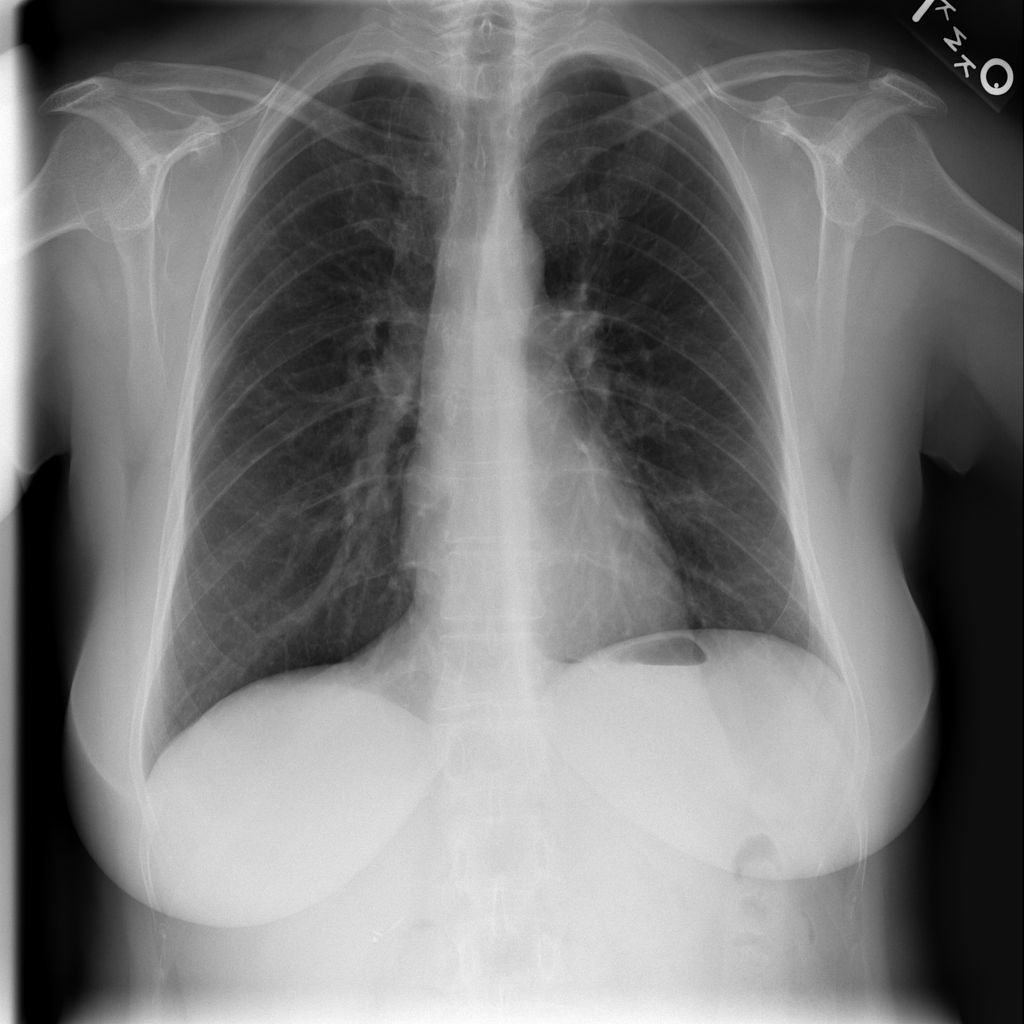

PAT-C77C · IMG-003Fibrosis

PAT-C77C · IMG-003

PA